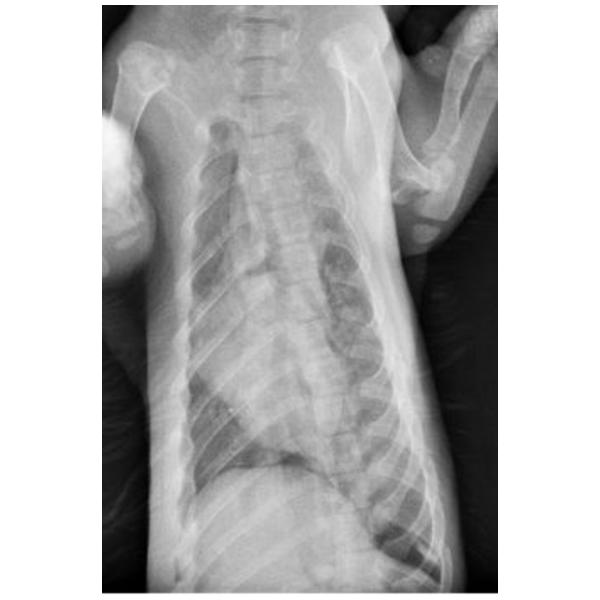

牙齒尚未換成恆久齒。全身長64cm、未含尾長40 cm、胸20 cm、前腳長10cm、後腳長9cm。外表無明顯外傷,頭顱變形,口腔、鼻腔內有血液。

頭骨骨折、下顎骨折、多處肋骨骨折、氣胸。